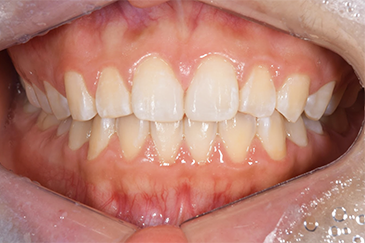

Before

After

| 主訴 | 前歯の隙間をなおしたい |

| 治療期間 | 30分 |

| 治療費 | ダイレクトボンディング2歯 22,000円×2(税込み) |

| リスク・副作用 | かみ合わせがとても強い方の場合、稀に割れてしまうことがあります。 |

| 先生からの提案 | 上の前歯2本に虫歯はなく健康な歯を削りたくないため、 歯を削らずに自費のプラスチックの材料で治療しました。 |